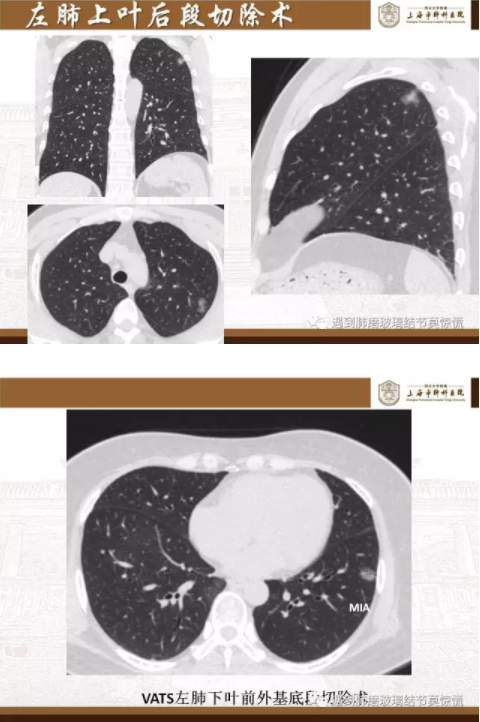

下面就我们的病例分析一下怎么进行肺段切除。

MIA= 微浸润腺癌   IA= 浸润性腺癌   AIS= 原位腺癌   AAH= 不典型腺瘤样增生